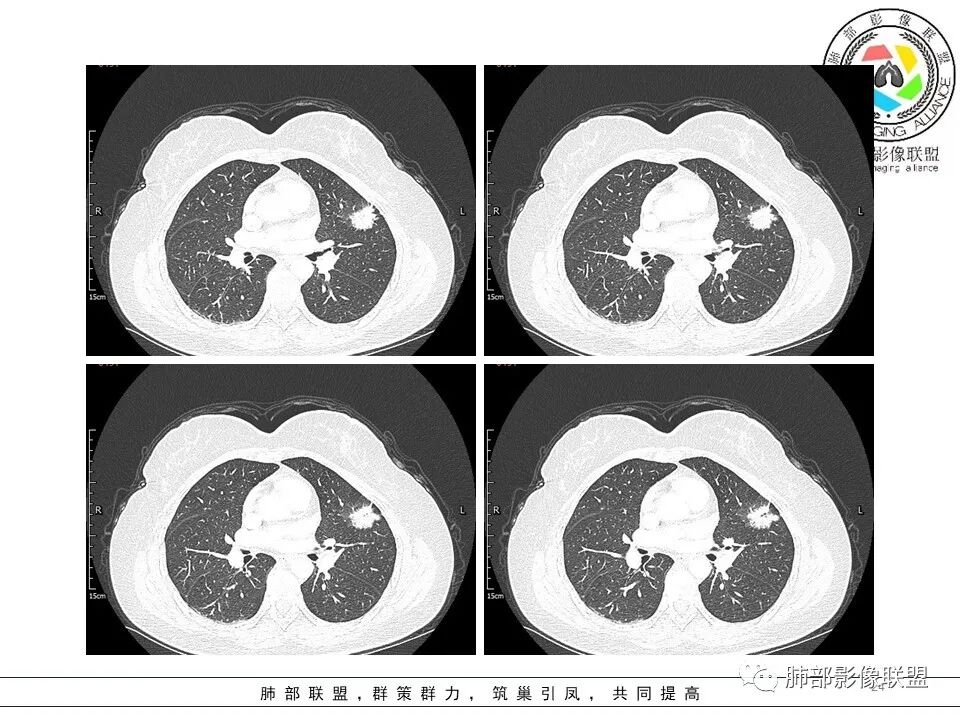

分叶结节,内部结构杂乱,边缘板刷样毛刺,GGO边界清楚

胸膜牵拉

月牙铲?

常规要考虑腺癌

左肺上叶胸膜下不规则结节影,分叶、粗短毛刺,胸膜牵拉等,像个“刺头”。

未见钙化,也未显示液化坏死或空洞。

1.病灶周围向几个方向膨出的边界清楚的磨玻璃影,这些磨玻璃影时隔几个月依然,几乎可以排除出血及一般的炎性改变。

2.病灶的胸膜牵拉线与其间病灶胸膜侧的磨玻璃边构成朝向胸壁的“月牙铲”结构,这种影像学表现某种程度上反映出病理学特征——病灶收缩+小叶间隔阻挡。

结合临床,应当高度怀疑浸润性肺腺癌!

在影像上观察到肿块或磨玻璃结节一侧的内凹,像个月牙铲形态,病理是肿瘤生长受到小叶间隔阻挡并受肿瘤内部的收缩力形成,王兆宇老师称之为“月牙铲”!对诊断肺腺癌较有特异性。